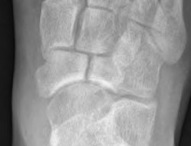

Acute displaced navicular fracture